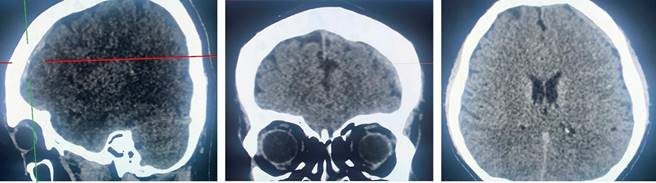

Hombre de 37 años sin antecedentes de relevancia para el caso. Ingresa por lesión de menisco, previo al procedimiento quirúrgico, se aplica anestesia neuroaxial con aguja calibre 20, en posición decúbito lateral derecho, a nivel de L2-L3, 48 horas posteriores presenta fotofobia, cefalea holocraneal intensa, 10 de 10, acompañada de náusea, vómito, que mejora con la posición decúbito, con criterios clínicos para diagnóstico de cefalea postpunción: orbitaria, temporal y acompañada de cervicalgia. Al ser la fotofobia un síntoma no común, se solicita estudio de tomografía axial computarizada (TAC) de cráneo simple, corroborando la presencia de un hematoma subdural (Figura 1).

Figura 1: Tomografía axial computarizada de cráneo simple. Se reporta hipotensión intracraneal hematoma subdural laminar en la región frontal izquierda, disminución en la amplitud de los ángulos interpeduncular y pontomesencefálico, así como disminución en la distancia mamilopontina.